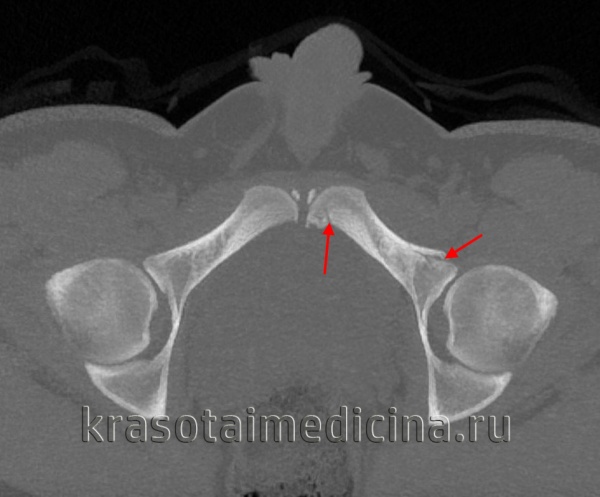

Для уточнения диагноза выполняют обзорную рентгенографию таза и рентгенографию поврежденного сустава в трех дополнительных проекциях. По возможности пациента направляют на КТ таза, поскольку эта методика позволяет более точно оценить тяжесть травмы и характер смещения отломков. Диагностическая ценность компьютерной томографии возрастает при повреждениях задней колонны и оскольчатых переломах.

Задняя опора и передняя губа лучше просматриваются на снимке в наружной косой проекции под углом 45°, в то время как задняя губа и передняя опора — на снимке во внутренней косой проекции под углом 45°. Кроме того, переломы заднего столба будут искажать подвздошно-седалищную линию, в то время как переломы передней опоры приведут к деформации подвздошно-лонной линии. Центральные переломы вертлужной впадины лучше выявляются на задней косой проекции. Некоторые виды переломов таза нередко сочетаются с переломами вертлужной впадины, которые не всегда легко выявить рентгенологически.

Прямая проекция тазобедренного сустава (вертлужной впадины). У больного с подозрением на перелом следует тщательно осмотреть эти линии. При скрытом переломе может наблюдаться смещение только одной из этих линий